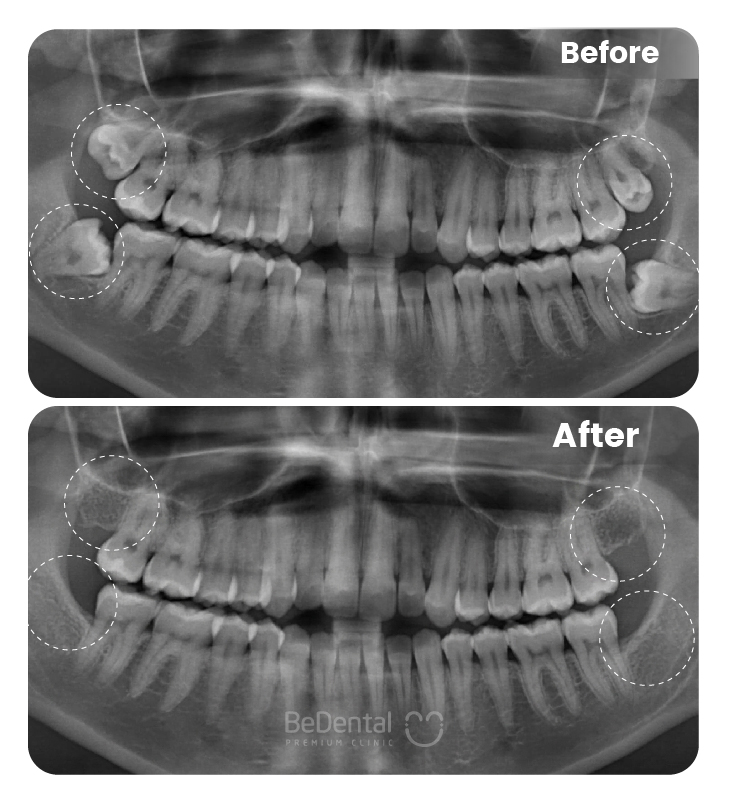

Nhổ răng khôn là thủ thuật nha khoa nhằm loại bỏ răng số 8 mọc lệch, mọc ngầm hoặc gây đau nhức, viêm nhiễm. Với sự hỗ trợ của công nghệ hiện đại và gây tê an toàn, quá trình nhổ răng diễn ra nhanh chóng, hạn chế đau, giúp ngăn ngừa biến chứng và bảo vệ sức khỏe răng miệng lâu dài.